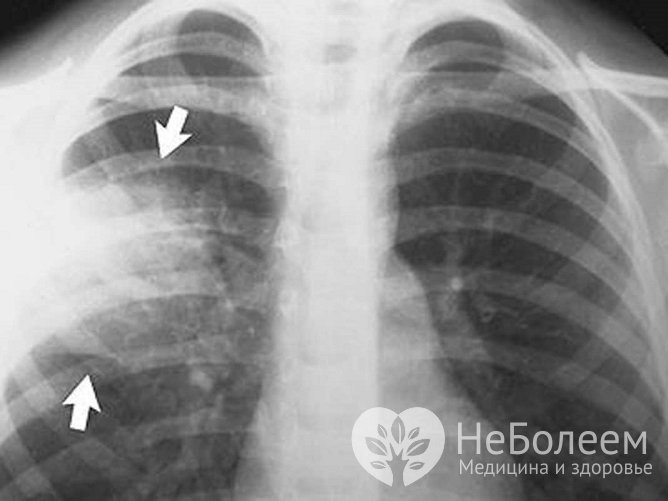

Одним из наиболее информативных инструментальных методов диагностики крупозной пневмонии является рентгенологическое исследование. Для подтверждения диагноза может потребоваться компьютерная или магниторезонансная томография.